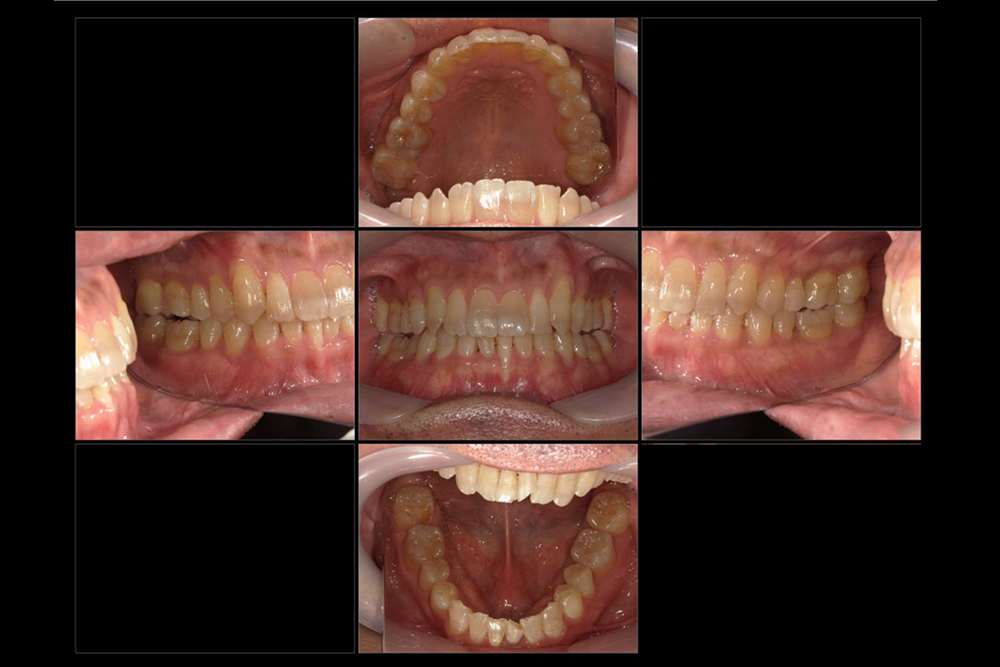

2024年7月

浜松市中区の症例紹介 マウスピース矯正

2025年8月

初診時年齢:20代女性

治療:前歯部矯正

治療法:マウスピース型矯正装置(インビザライン)

治療期間:1年1ヶ月

費用:462,000円(税込)

リスク・副作用:装置装着による違和感、歯の移動時の痛み